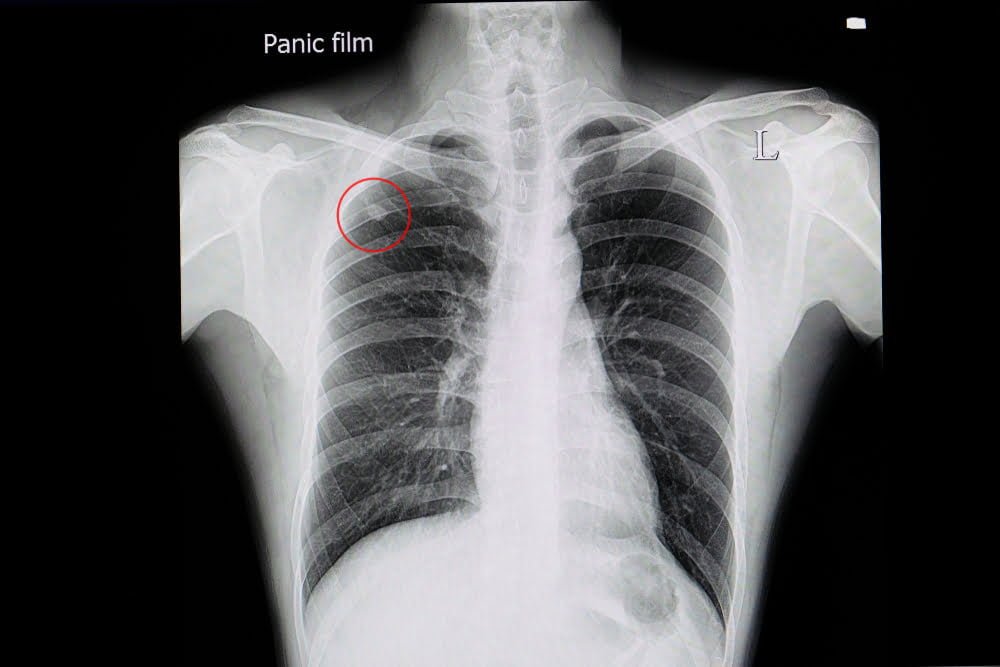

DIAGNOSI PRECOCE DELLA POLMONITE Calabrese Medical Specialist

Nódulos no pulmão causas, sintomas e tratamento Clínica TxTórax